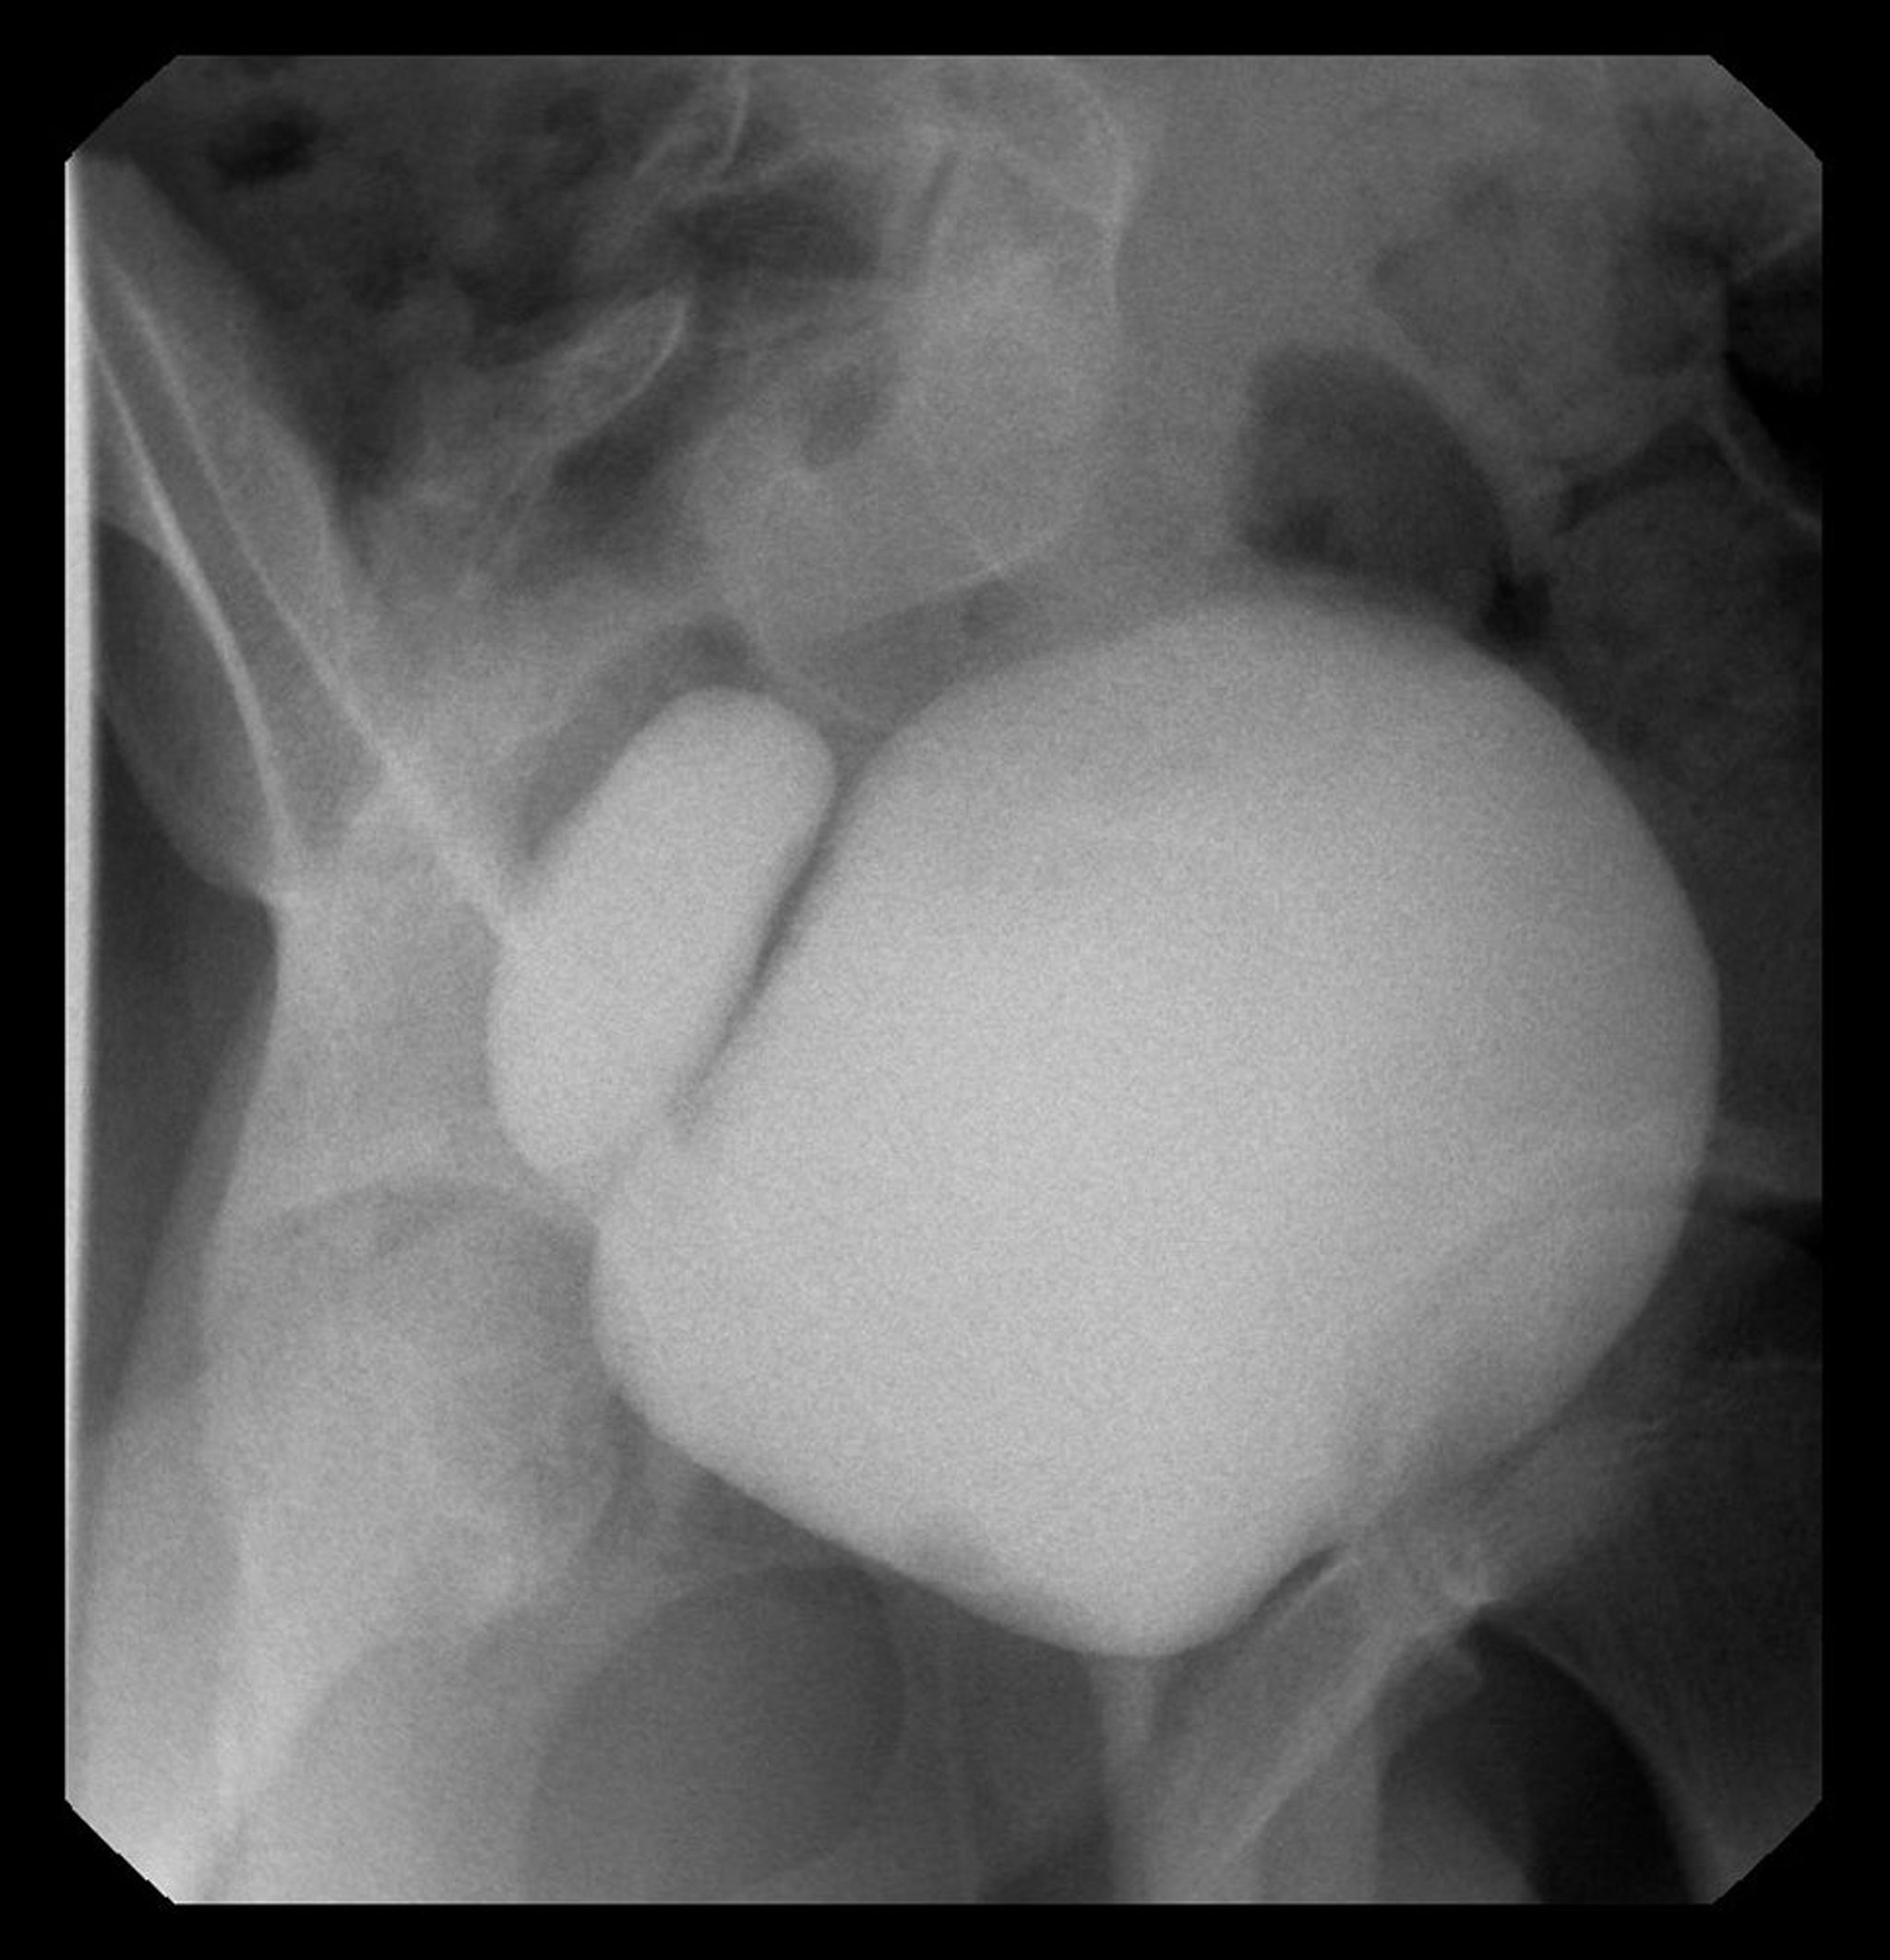

Diverticules vésicaux

Cette image montre un cystogramme avec diverticule de la vessie à droite.

Image courtoisie de Drs. Ronald Rabinowitz et Jimena Cubillos.